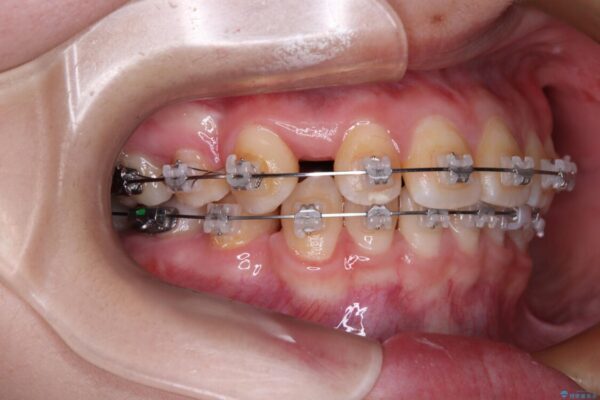

治療途中

• 転勤でも安心して治療継続 抜歯スペース閉鎖と深い噛み合わせ改善のワイヤー矯正 治療途中画像